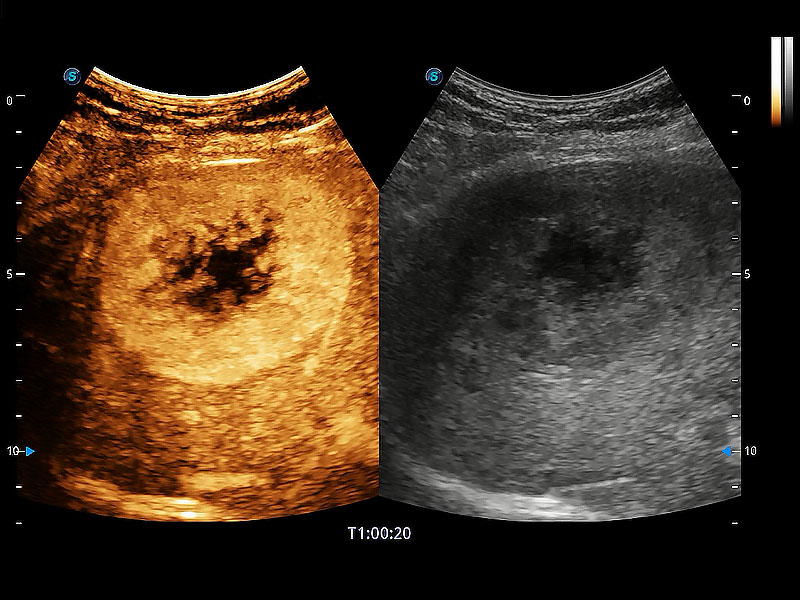

了若指掌 腹部/浅表解决方案

高性能和先进的临床应用工具可以为动物医生提供临床信心。ProPet 80 搭载了先进的腹部和浅表应用工具,帮助医生在日常临床实践中发挥前所未有的作用。

• Micro F 显微血流成像

极大提升超低速微细血流的检出能力,同时更精准地滤除软组织和超声信号,为兽用医生提供以往无法通过常规血流获得的疾病诊断信息。

• Bright Flow 立体血流成像

在传统二维血流成像的基础上,呈现血流的立体感,具有动感的生命力之美。即便是微小的血管也能轻松应对,提高了血流的视觉敏感性。

(犬)肝脏

(猫)胆囊

(犬)肾脏显微血流